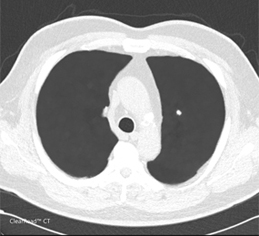

| Clearread CT 人工智慧電腦斷層肺結節分析判讀系統 |

| ClearRead CT是一種電腦輔助檢測系統,用於識別和標記注意區域(Regions of Interest,ROI)。ClearRead CT系統適用於所有結節類型,包括實質(solid)、非實質(sub-solid)和毛玻璃樣(ground glass)結節,其尺寸介於5mm到30 mm之間。本系統僅限於每個CT系列(CT series)標記被視為值得檢查的5個 ROI。ClearRead CT的使用可以減少疏漏錯誤。系統的比較元件允許ROI與先前掃描的時間先後比較,並提供隨時間的體積變化。 |